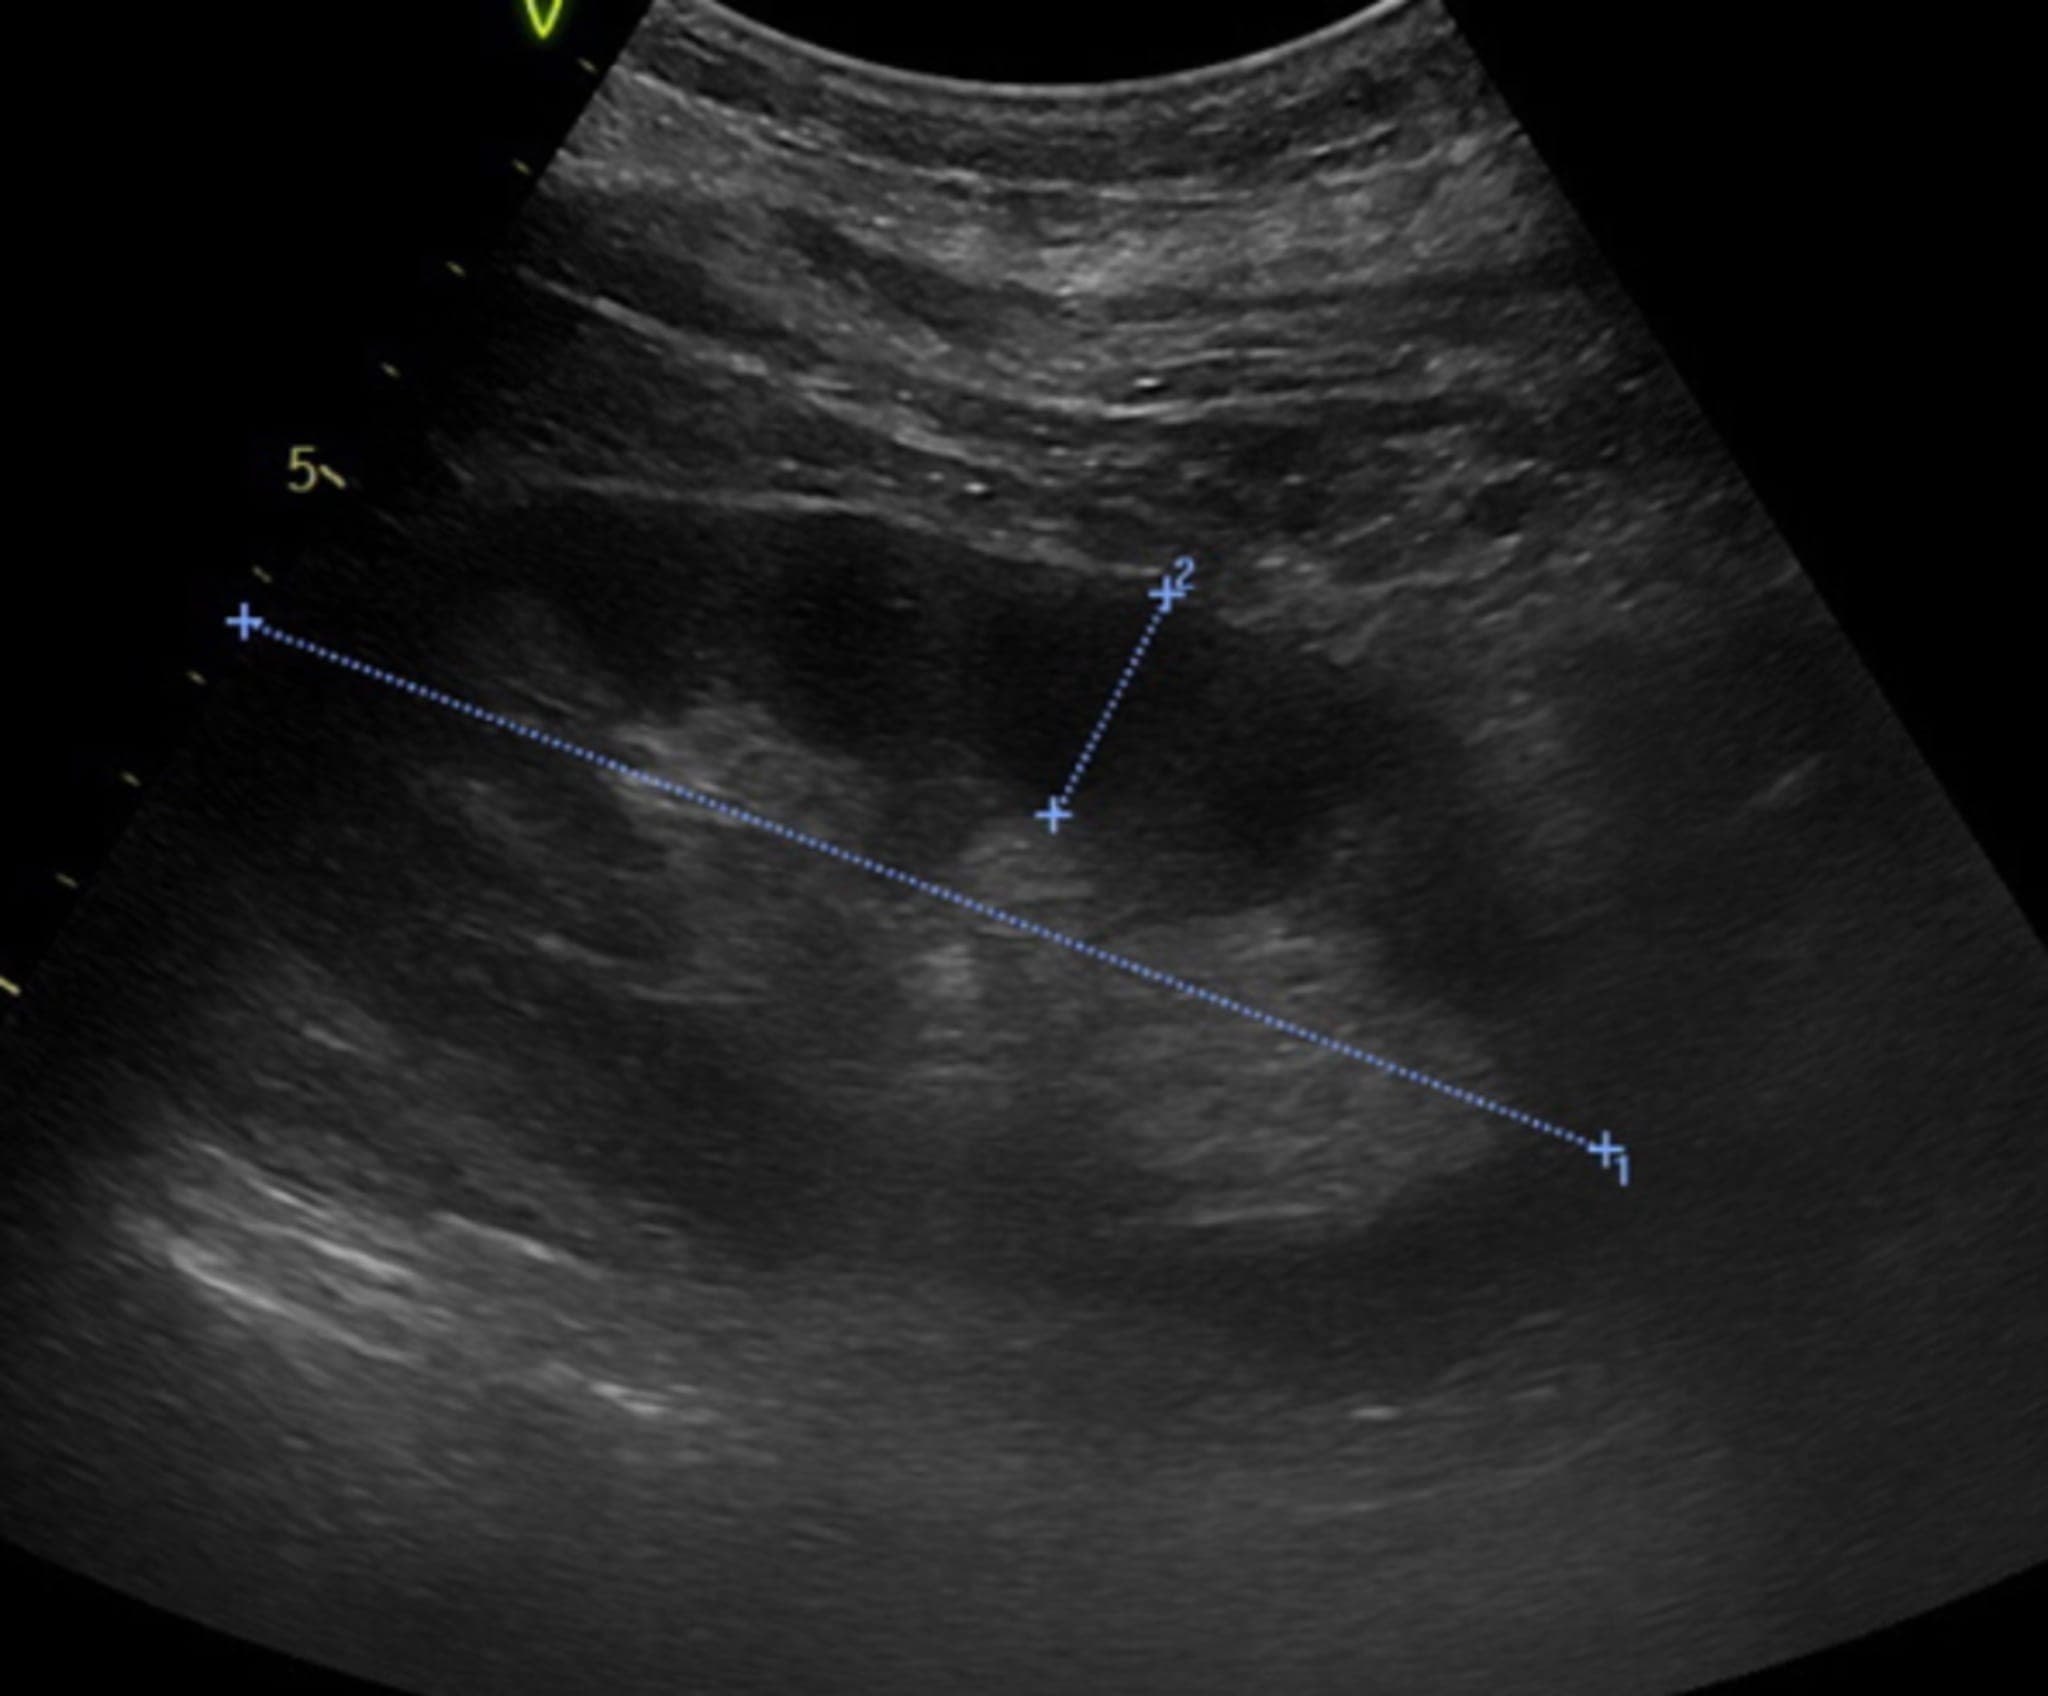

Entsprechend des Kreatinin-Anstieges wird das AKI als Stadium AKIN 3 bewertet. Bei der Genese stellt sich die Frage, ob die Ursache der Nierenschädigung prä-, intra- oder postrenal ist. In der Bildgebung (CT und Sonografie) gibt es keine Hinweise für eine Harnstauung oder eine Uretherobstruktion, sodass eine postrenale Ursache ausgeschlossen werden kann. Eine prärenale Ursache scheint möglich – denn offenbar hatte die Patientin einen deutlichen Infekt. Jedoch gibt es keine Hinweise für eine Volumendepletion, sodass eine intrarenale Ursache am wahrscheinlichsten ist.

In der Bildgebung finden sich zwei normal aussehende Nieren, Leber und Pankreas sind unauffällig, ebenfalls unauffällige Gefäßabgänge arteriell und venös und eine etwas verdickte Dünndarmschlinge.